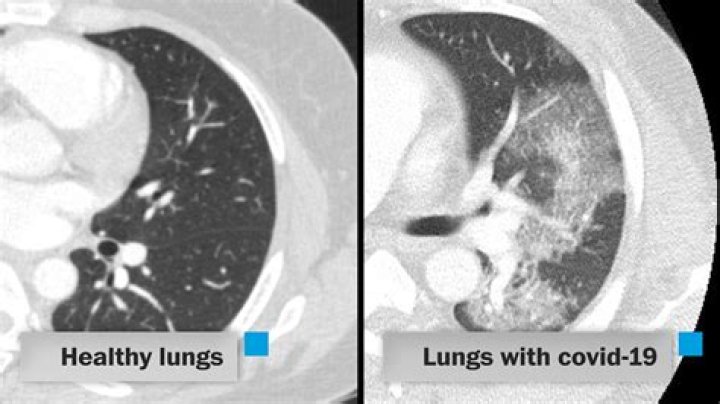

About 14% of COVID-19 cases are severe, with an infection that affects both lungs. As the swelling gets worse, your lungs fill with fluid and debris. You might also have more serious pneumonia. The air sacs fill with mucus, fluid, and other cells that are trying to fight the infection.

The body replaces cells damaged by the virus with scar tissue, which is thick and stiff. This can result in a condition called “pulmonary fibrosis”, which has been seen in people with COVID-19 and is probably more likely to develop if the lungs are severely affected by the infection.

While most people recover from pneumonia without any lasting lung damage, the pneumonia associated with COVID-19 can be severe. Even after the disease has passed, lung injury may result in breathing difficulties that might take months to improve.